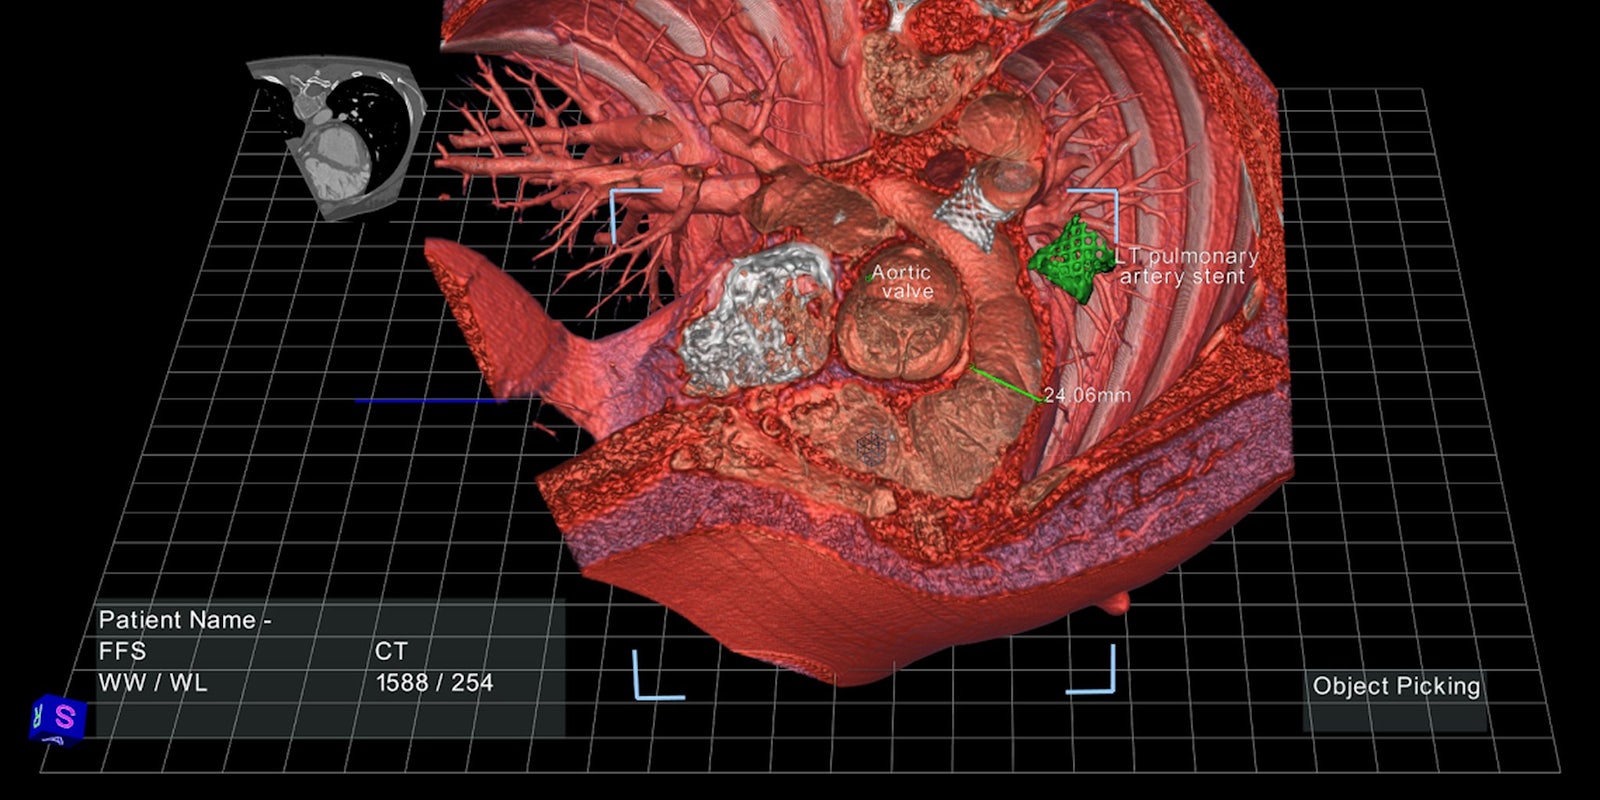

The software can transform data from ultrasound, CT, and MRI scans into three-dimensional anatomical models projected onto a computer screen, with which doctors can interact using a stylus. A doctor can, for example, click on one brightly colored segment of the virtual colon to scan the interior tissue for soft, spongy polyps, or point and click to extract an aneurysm from deep inside a virtual brain.

Doctors can also use these virtual models to create surgical plans without excessive exploratory slicing and dicing. Such plans are still essentially drawn up on a sheet of paper, which can only offer so much insight about a patient’s actual anatomy. It would be much more simple, Aguirre said, if a surgeon could have a sense of precisely how far they’ll have to reach inside a child’s chest cavity to rebuild a detached pulmonary artery.

In a clinical trial conducted at Stanford, EchoPixel’s technology allowed radiologists and surgeons to do just that, working together to draw up a three-dimensional surgical plan with a 40 percent reduction in interpretation time.

And those surgical plans can be saved and shared, Aguirre added. “Let’s say there’s a pediatric patient with a congenital heart defect in Oklahoma and the surgeons aren’t sure if they can actually treat this patient. Using our technology, they can send the data to our expert at Stanford, and he can draw the surgical plan he feels is best for this patient and send it back to the surgeons in Oklahoma. We see this sharing of information as something that’s very, very important.”